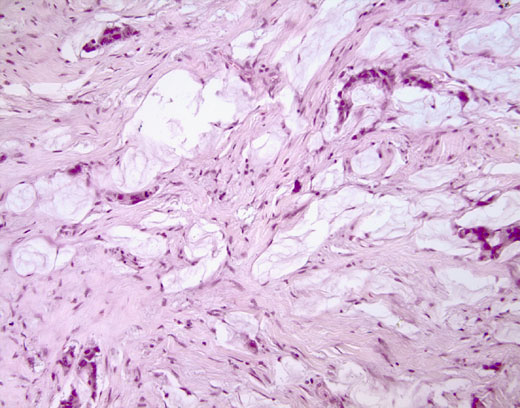

Cross-section #21 - 20X

click on the slide photo to see 40X magnification